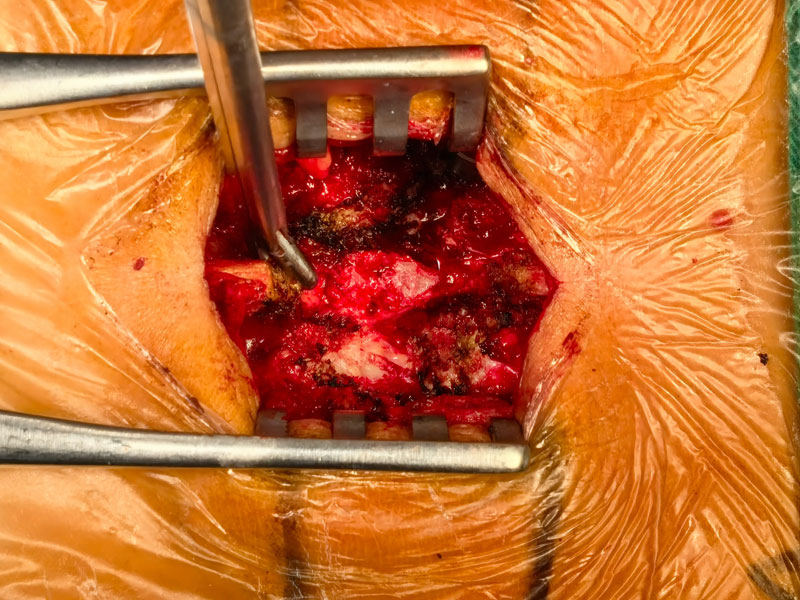

The multicenter clinical trial for Absorbable Bone Wound Hemostasis Mud (ABHM), jointly developed by our company and Zhongnan Hospital of Wuhan University, has recently been successfully completed. As of last week, a total of 218 clinical cases had been performed across participating clinical centers, with full data collection and follow-up for all cases expected to be finalized by next week.

During the trial, ABHM demonstrated excellent clinical performance and safety. Its biodegradable properties and ease of use were highly praised by surgical experts from multiple clinical centers. The product rapidly achieves hemostasis by mechanically sealing bone wound surfaces, and it degrades completely within four weeks. This effectively avoids complications associated with traditional bone wax, such as impaired bone healing, foreign body granuloma, chronic inflammation, and infection—offering a safer and more physiologically compatible solution for bone wound management.